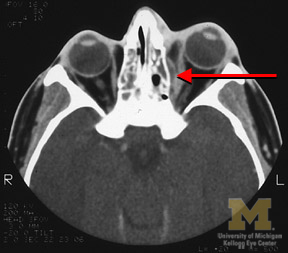

Orbital cellulitis is a bacterial infection of the periocular tissues. Cellulitis restricted to the soft tissues anterior to the orbital septum (a connective tissue curtain that divides the anterior third from the posterior two thirds of the orbit) is called “pre-septal cellulitis.” It is much less serious than infection that extends behind the orbital septum, called “post-septal cellulitis.”

The infection usually starts in the paranasal sinuses, especially the ethmoid. It is especially common in children.

The doctor will ask for sino-orbital imaging studies to rule out sinusitis, orbital subperiosteal abscess, or tumor. Patient usually requires treatment with intravenous antibiotics. If there is Subperiosteal abscess, it may require surgical drainage.